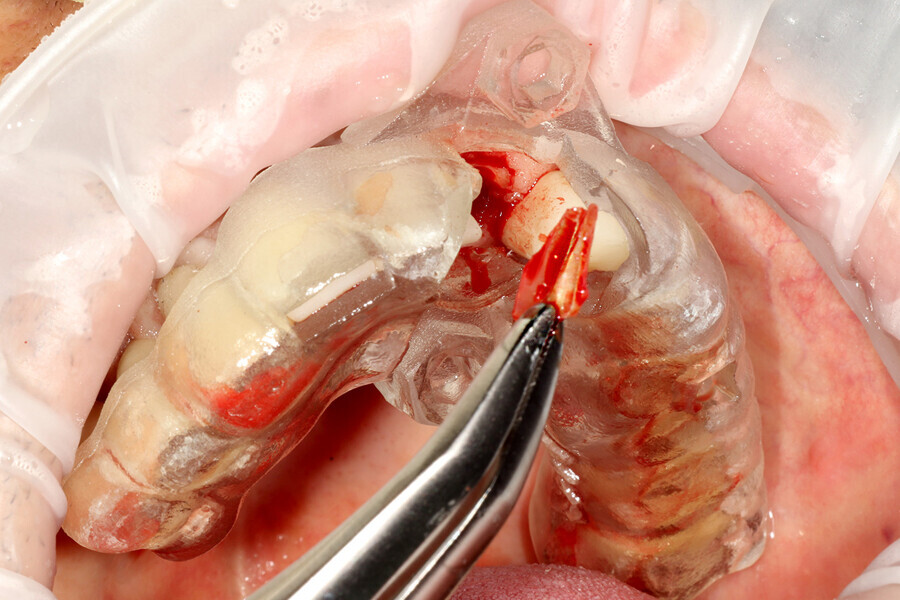

Fig. 20: The sectioned palatal root was carefully removed.

Fig. 21: A periapical radiograph confirmed that the palatal root and all the gutta-percha had been completely removed.